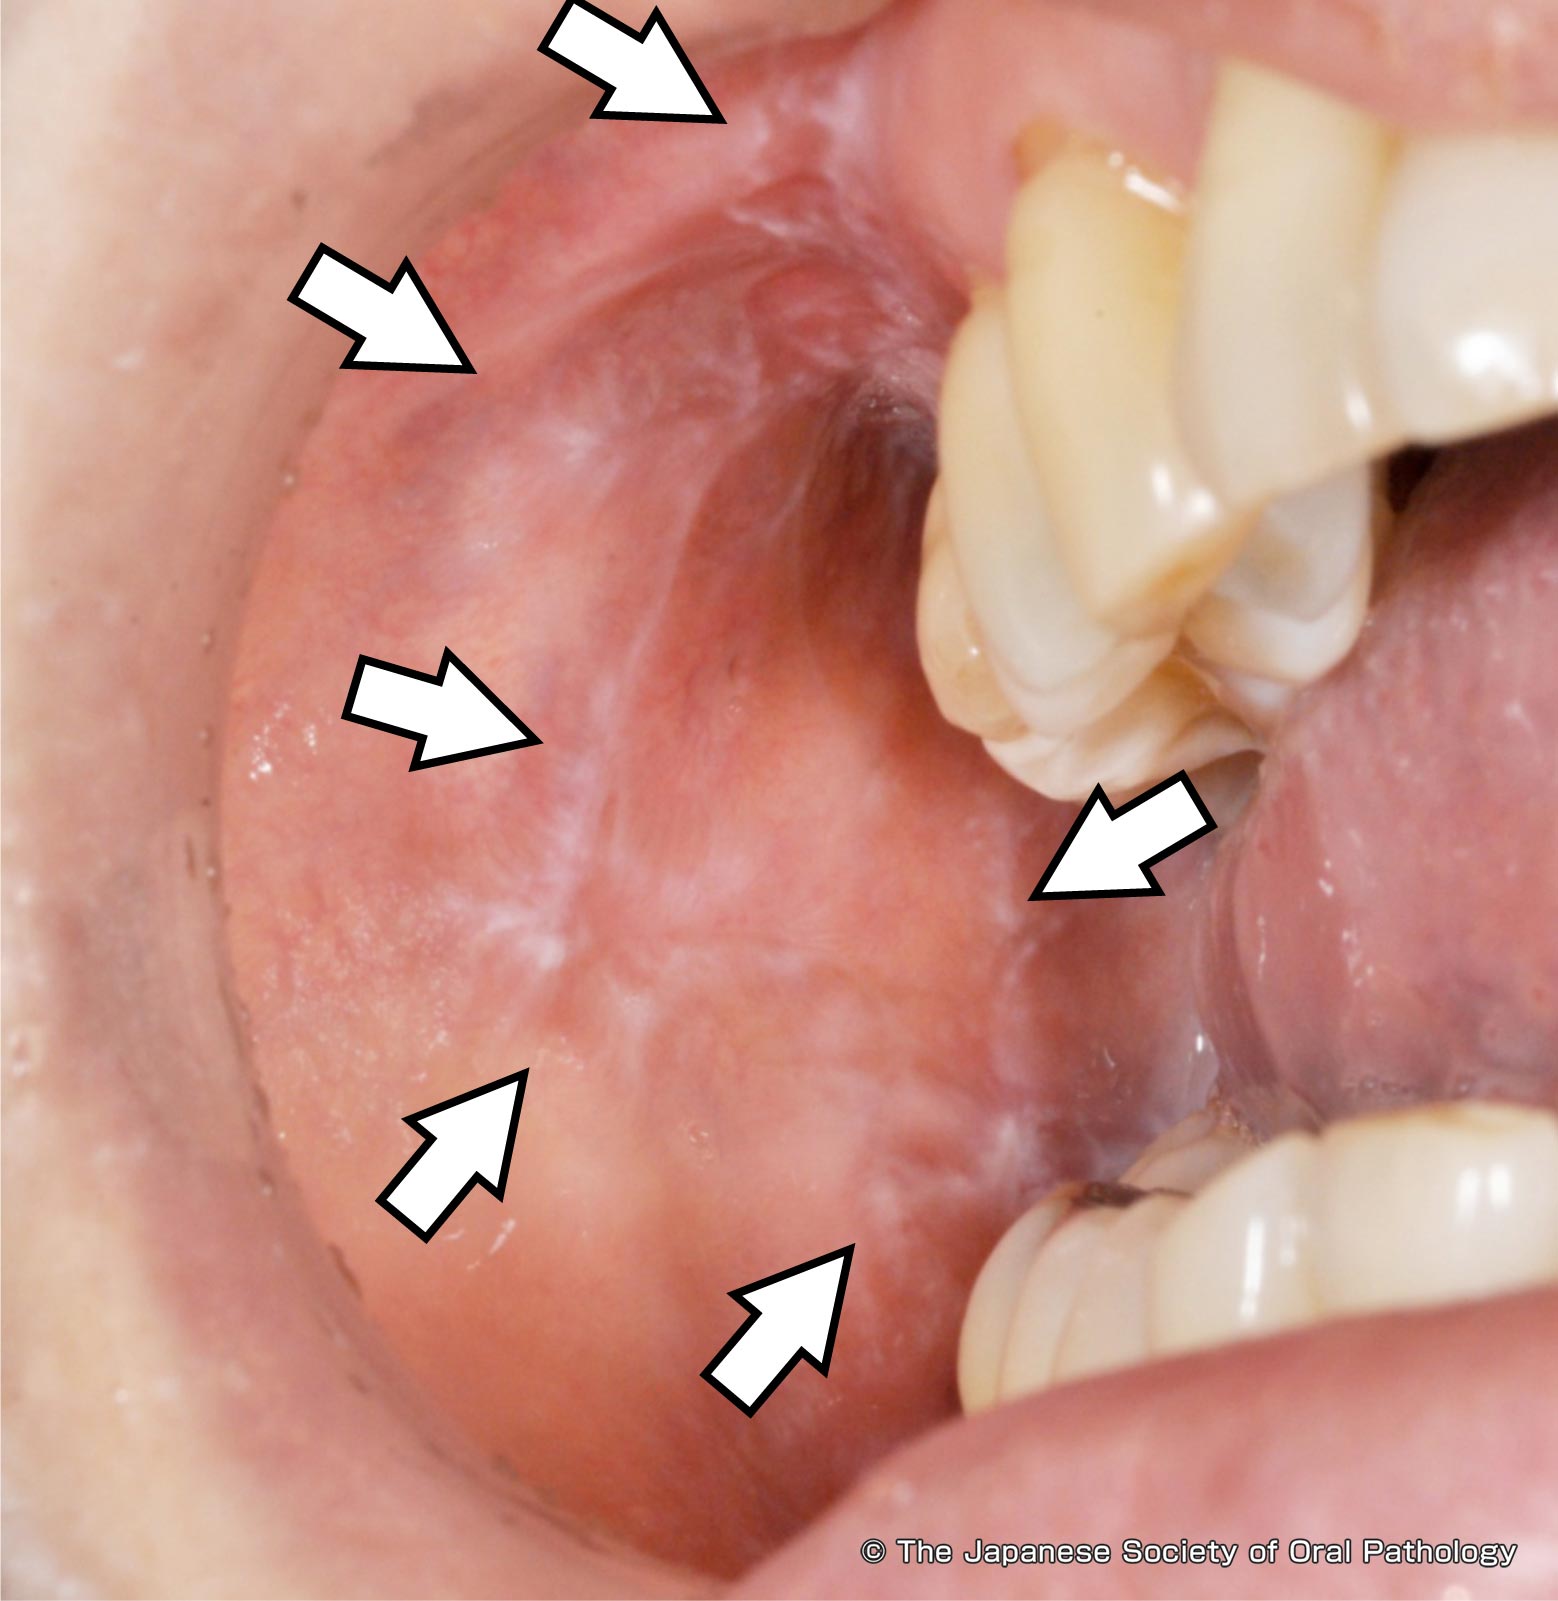

第5章 口腔粘膜の病変 扁平苔癬4 7。